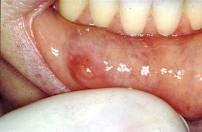

问题 以下涎腺肿瘤最易发生种植复发的肿瘤是 ( )

选项 A.肌上皮瘤 B.嗜酸细胞腺瘤 C.多形性腺瘤 D.腺淋巴瘤 E.基底细胞腺瘤

答案 C